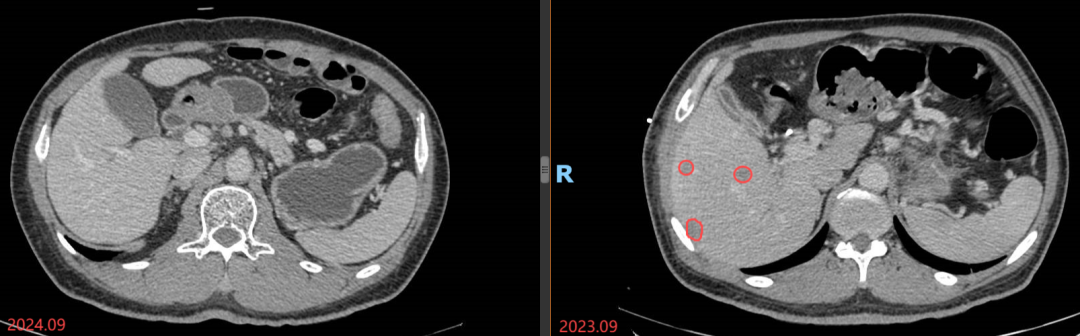

第四步:联合靶向,精准打击

老木的梗阻性黄疸较之前明显好转,这次治疗恢复了标准剂量。根据老木的基因检测结果,从精准诊治的角度,杭医生采用化疗联合靶向治疗的方式,老木的肿瘤得到了明显的控制,肝内多发转移灶基本缩小到了0.5cm以下!

时间终于来到了国庆前夕。2024年9月24日,老木完成了最近一次的治疗,1年多的时间,老木肝脏上的肿瘤快要达到消失不见的程度,黄疸问题也完全解决,胆汁的引流袋也早已拿掉。